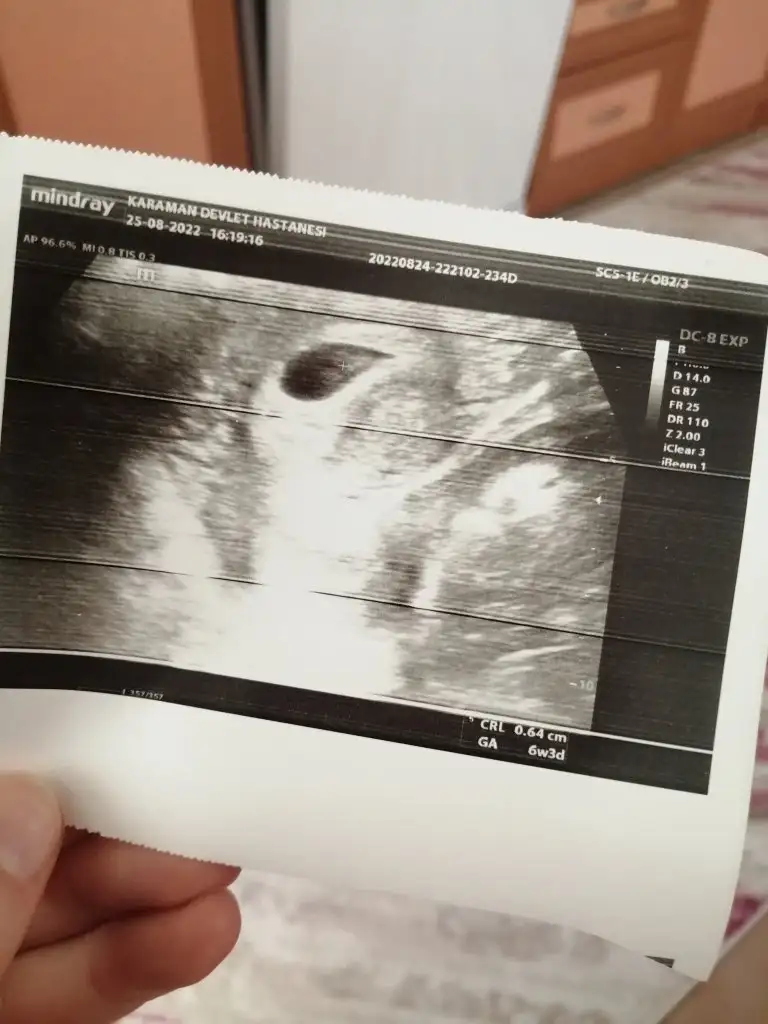

Bebeğin 0.64 cmEki Görüntüle 3118881

Anladım çok teşekkür ederimBebeğin 0.64 cm

6+3 gün ile uyumlu canım

At canım bakalımKızlar hastaneden geldim bebeğimin kalp atışını duydumdoktor gayet sağlıklı 1 ay sonra tekrar gel dedi hiç bir şey söylemedi başka. Siz ultrason fotoğrafından anlar mısınız?